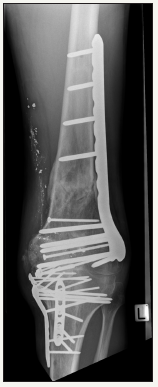

Figure 6: Four month post-operative AP X-Ray showing healed fractures.

Figure 7: Four month post-operative lateral X-Ray showing healed fractures and fixed flexion deformity of knee.

A lateral locking plate was then placed to definitely fix the more proximal extension of the fracture. The patient’s ACL and PCL were ruptured but were not reconstructed as it was thought that instability would unlikely be an issue. The wound was primarily closed. The patient was placed into a locked knee brace to facilitate wound healing. At the two week mark the wound was well healed and the brace was unlocked to allow active knee range of motion although the patient was kept strictly non-weight bearing. At most recent follow-up (four months) his knee was stiff with range of motion 10-60 degrees but with no signs of deep infection and all fractures look to have united (Figures 6 & 7). Although pain free it is likely he will require early knee arthroplasty.